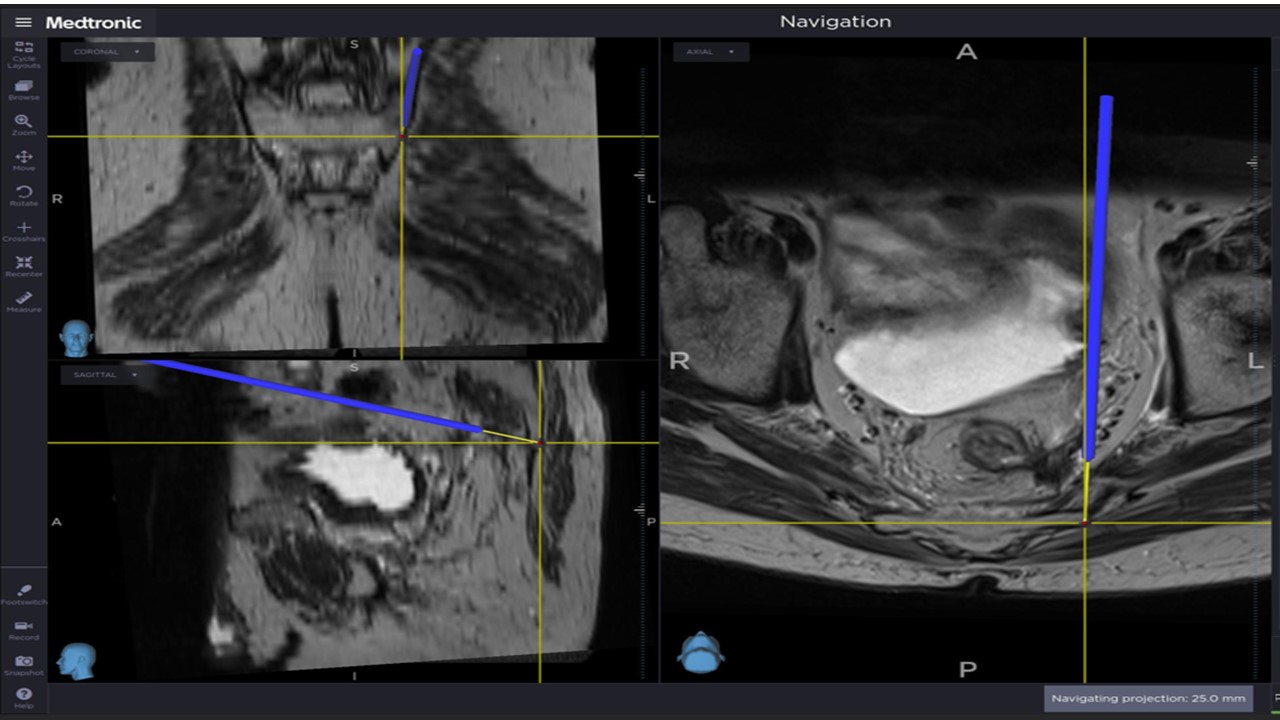

Image of the navigator during intraoperative field testing